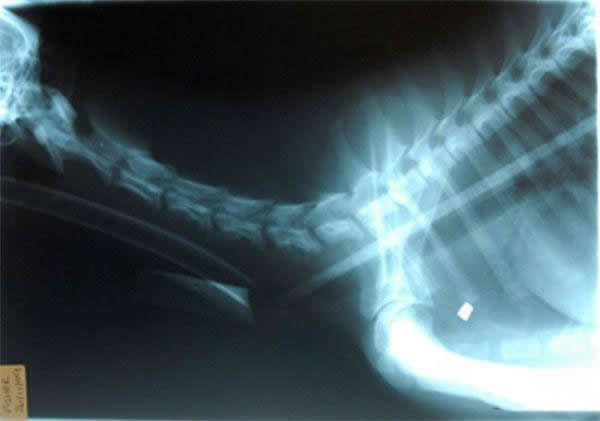

Toys, nails, cell phones, there is an incomplete list of items that are found in the stomachs of four-legged friends